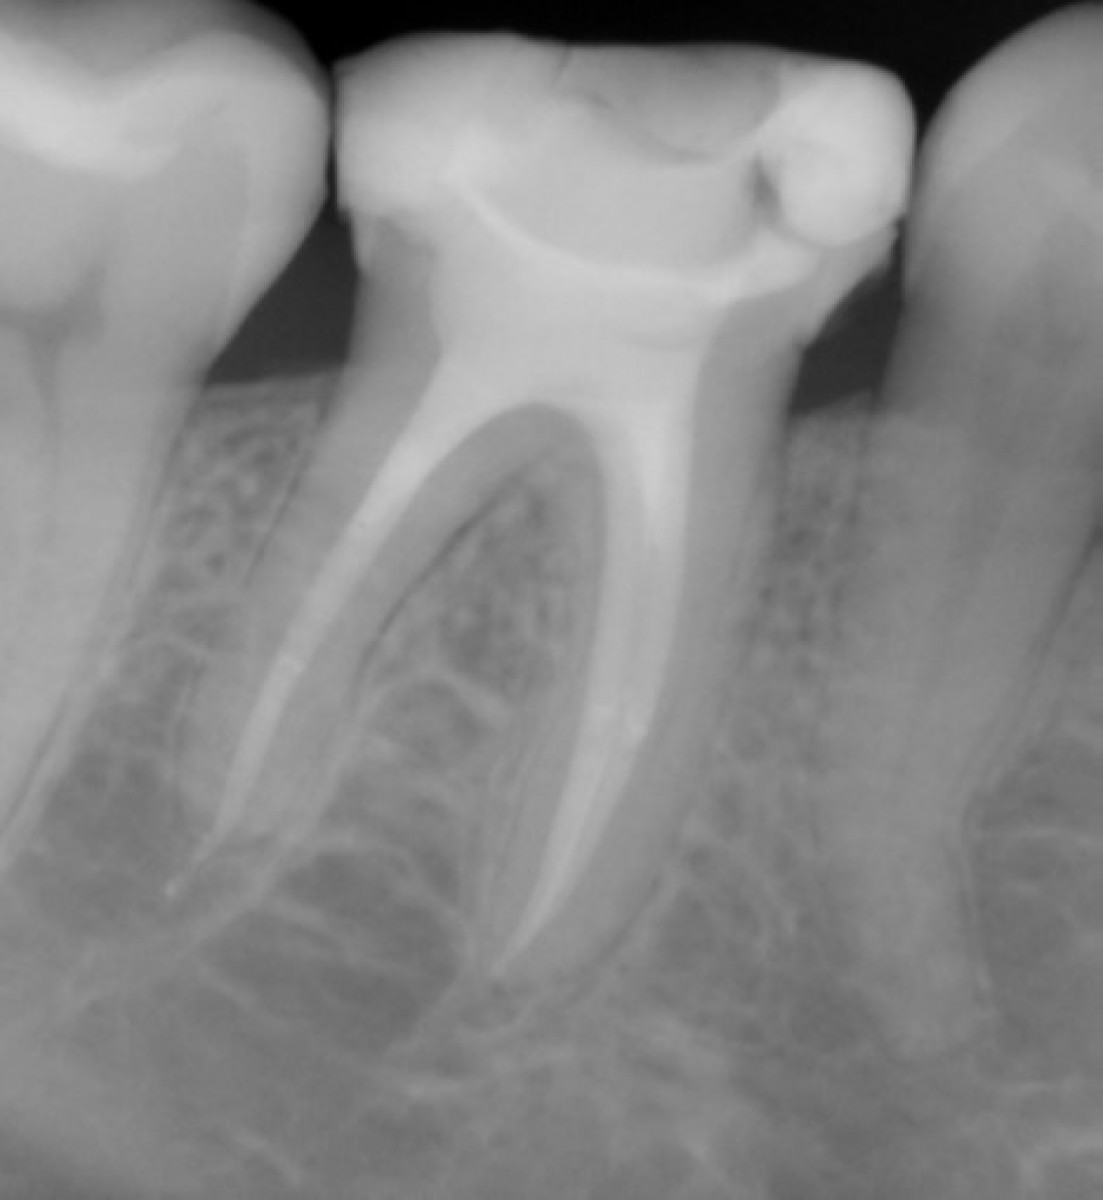

Case Report Endodontics . This report illustrates a rare case of a geminated maxillary right second molar tooth. The journal of endodontics, the official journal of the american association of endodontists opens in new window , publishes. This case report demonstrates the use of dynamic navigation to remove a post from under a zirconia crown for the retreatment of a failing root canal procedure. This case report discusses the diagnosis and successful endodontic management of two cases showing unusual root canal configuration in a. This case report was prepared according to the price 2020 guidelines.